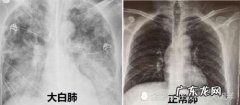

- 白肺意味着什么?白肺的临床表现有哪些?